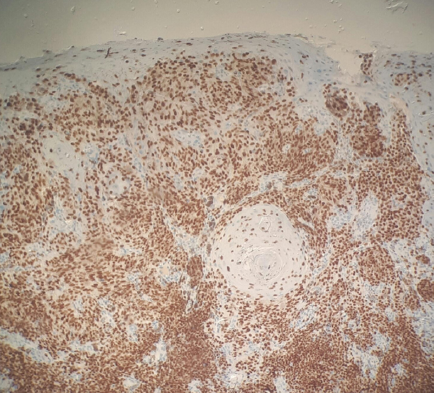

A oroscopia revelou placa enegrecida no palato duro direito, medindo cerca de 1cm, com área ulcerada, acompanhada por lesões-satélites, e placa enegrecida na gengiva superior direita, com aproximadamente 2,5cm (Figuras 1 e 2). O exame clínico não apresentou outras lesões suspeitas nem linfonodos cervicais palpáveis. A tomografia computadorizada de crânio, pescoço, tórax, ultrassonografia de abdome e exames laboratoriais não mostraram achados significativos. Procedeu-se à biópsia incisional que apresentou neoplasia de crescimento infiltrativo, constituída por células anaplásicas, contendo grande quantidade de melanina nos citoplasmas, com intenso grau de pleomorfismo e atipias nucleares (Figura 3). O perfil imuno-histoquímico foi compatível com melanoma melanótico maligno infiltrativo com coloração positiva de HMB-45 e melan A (Figura 4).

Histologicamente, as células tumorais são caracterizadas pela proliferação de melanócitos atípicos, e os parâmetros avaliados incluem presença ou ausência de melanócitos no tumor; morfologia celular (epitelioide, fusocelular, plasmocitoide ou mista); organização celular (sólido, alveolar, organoide ou pagetoide); presença de necrose, invasão perineural e perivascular e profundidade da invasão tumoral.7,10 Devido à falta de marcos histológicos análogos entre a pele e mucosa oral, o diagnóstico da profundidade ou espessura dos tumores, conforme definido por Clark e Breslow, não é aceito na prática cotidiana do MMO.4,7 Portanto, tem sido implicada uma classificação com base no padrão histopatológico do tumor: melanoma in situ, limitado à epiderme e sua junção com o tecido conjuntivo (15%); melanomas invasivos, que se estendem para o tecido conjuntivo (30%); e melanomas com um padrão combinado entre invasivo e in situ (55%).1,5,8,10 O uso de coloração imuno-histoquímica é útil para ajudar na confirmação diagnóstica.9 Os marcadores envolvidos no diagnóstico de melanoma são S-100, HMB-45, melan-A e tirosinase.7,8 O S-100 é sensível (97%-100%), mas não específico (75%-87%); HMB-45 e melan-A são considerados marcadores mais específicos.8